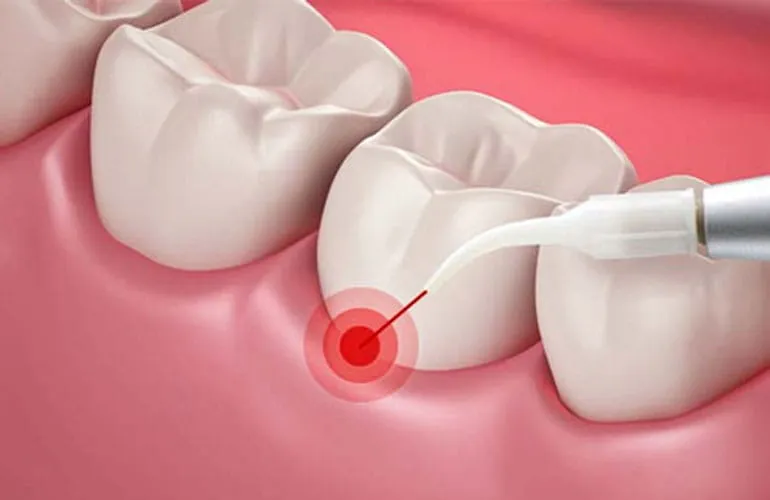

لیزر درمان پریودنتال مجموعهای از تکنیکهای کمتهاجمی است که با انرژی لیزر روی بافت نرم و گاه سخت ناحیه پریودنتال اعمال میشود تا بار میکروبی پاکتها کاهش یابد، بافتهای بیمار هدف قرار گیرد، خونریزی کنترل شود و ترمیم بافتی بهبود یابد. در سالهای اخیر، فناوری لیزر بهصورت گستردهتری در کنار درمانهای استاندارد (مانند SRP، جراحی فلپ، بازسازی استخوان و …) بهکار میرود و بسته به مورد، میتواند به کاهش عمق پاکت، بهبود خونریزی حین پروبینگ و راحتی بیمار کمک کند. مرورهای جدیدتر (تا ۲۰۲۵) نیز مزایای بالقوهای مثل اثر ضدباکتریایی، برداشت بیوفیلم و احتمالا اثرات فتوبیومادولیشن را گزارش کردهاند؛ هرچند همچنان تاکید دارند پروتکل باید مبتنی بر شواهد و در کنار درمانهای مکانیکی باشد.

کار با لیزر بر اساس پروتکل: هدایت فیبر/هندپیس بهصورت کنترلشده در پاکتها، کاهش خونریزی و کاهش بار میکروبی.

ایجاد شرایط ترمیمی بهتر: بافتهای بیمار برداشته/کوآگوله میشود تا شرایط چسبندگی بهتر فراهم گردد.